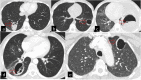

Hydatid cyst caused by the larval form of Echinococcus is a worldwide zoonosis. The lungs and liver are the most common sites involved. While the lung parenchyma is the most common site within the thorax, it may develop in any extrapulmonary region including the pleural cavity, fissures, mediastinum, heart, vascular structures, chest wall, and diaphragm. Imaging plays a pivotal role not only in the diagnosis of hydatid cyst, but also in the visualization of the extent of involvement and complications. The aim of this pictorial review was to comprehensively describe the imaging findings of thoracic hydatid cyst including pulmonary and very unusual extrapulmonary involvements. An outline is also given for the findings of complications and differential diagnosis of thoracic hydatid cyst.